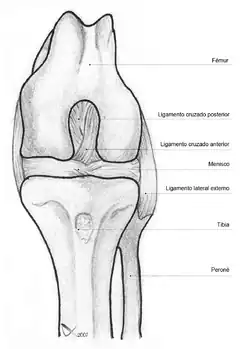

La rodilla está sustentada por fuertes ligamentos que impiden que sufra una luxación, siendo los más importantes el ligamento lateral externo, el ligamento lateral interno, el ligamento cruzado anterior y el ligamento cruzado posterior.[4]

Ligamentos

La rodilla esta sustentada por varios ligamentos que le dan estabilidad y evitan movimientos excesivos. Los ligamentos que están en el interior de la cápsula articular se llaman intraarticulares o intracapsulares, entre los que se encuentra el ligamento cruzado anterior y el ligamento cruzado posterior. Por otra parte los ligamentos que están por fuera de la cápsula articular se llaman extrarticulares o extracapsulares como el ligamento lateral interno y el ligamento lateral externo.[8][9]

Intraarticulares

- Ligamento cruzado anterior (LCA).

- Ligamento cruzado posterior (LCP).

- Ligamento yugal o ligamento transverso. Une los meniscos por su lado anterior.

- Ligamento meniscofemoral anterior o Ligamento de Humphrey. Del menisco externo al cóndilo interno del fémur.[10]

- Ligamento meniscofemoral posterior o Ligamento de Wrisberg. Del menisco externo al cóndilo interno del fémur, por detrás del meniscofemoral anterior.[11]

Extrarticulares